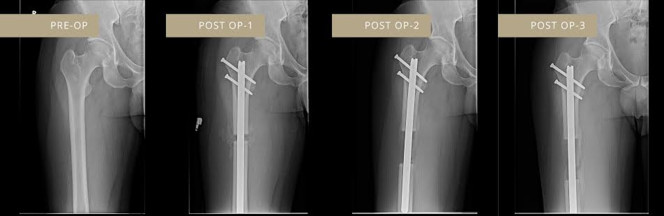

Тодруулбал, эхлээд үйлчлүүлэгчийн өвдөг таазанд мэс засал хийж ясыг нь хугалаад голд нь идэвхжүүлэгчээ суулгаж хаддаг байна. Үүний дараа алсын зайн удирдлагаар идэвхжүүлдэг агаад ясны ургалтыг тухайн хүний биеийн байдал, онцлогт тааруулан хянаж өсгөдөг аж. Гэвч хурдан өсөхгүй, өдөрт 1 мм-ээр өснө. Ийнхүү эмчилгээний явцад үйлчлүүлэгчийн өндөр 10-15 см-ээр нэмэгддэг. Ээ маш их өвдөлт өгдөг байна.

Зураг дээрх Ирвин Родригес гэх эр 165 см өндөртэйгөөсөө болоод байнга гадуурхагддаг байсан бөгөөд мэс засал хийлгэн 178 см өндөр болсон байна.